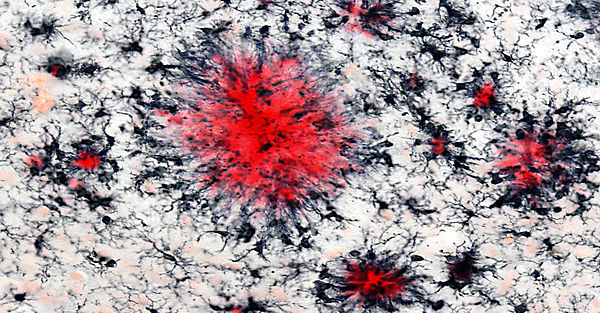

Eine Aktivierung des Immunsystems des Gehirns ist Teil fast aller neurologischer Erkrankungen und das Auftreten der Alzheimer-Demenz (AD) wurde kürzlich mit genetischen und epigenetischen Veränderungen von immun-relevanten Genen in Verbindung gebracht. Dies deutet auf eine signifikante Beteiligung des Immunsystems an der Alzheimer-Demenz hin. Die Immunantwort, die als Teil der Alzheimer-Erkrankung auftritt, wird hauptsächlich durch die Hirn-ansässigen Makrophagen, sogenannten Mikroglia, vermittelt, und diese Zellen sammeln sich besonders um die unlöslichen Ablagerungen an, die als Teil der Erkrankung im Gehirn auftreten. Jedoch sind verschiedene Aspekte der Rolle von Mikroglia in der Alzheimer-Pathogenese weiterhin ungeklärt. Weiterhin ist unklar, wie Entzündungsprozesse außerhalb des zentralen Nervensystems die Immunantwort des Gehirns beeinflussen können.

Zu diesem Zweck verwenden wir verschiedene Modelle der peripheren Entzündung und profilieren die Immunantwort der Mikroglia auf sekundäre Reize, einschließlich pathologischer Veränderungen in neurodegenerativen Krankheitsmodellen. Wir isolieren Mikroglia aus dem adulten und gealterten Gehirn und untersuchen deren molekulare Profile (transkriptional, epigenetisch) und Funktionen (phagozytisches Verhalten und Freisetzung entzündlicher Mediatoren). Zusammen mit der Unit Molekulare Bildgebung verwenden wir Multiphotonen-Mikroskopie, um mikrogliales Verhalten im lebenden Gehirn unter entzündlichen Bedingungen zu untersuchen.

In unserer Arbeitsgruppe haben wir vor kurzem gezeigt, dass Mikroglia in der Lage sind, sich an vorherige Entzündungsprozesse zu "erinnern" und ihre Immunreaktion an nachfolgende Reize anzupassen. Besonders bemerkenswert ist, dass diese langfristigen Anpassungen der mikroglialen Immunreaktion signifikante Auswirkungen auf die Hirnpathologie in Mausmodellen hatten. Darüber hinaus konnten wir zeigen, dass diese adaptive Reaktion auf der epigenetischen Umprogrammierung von Mikrogliazellen basiert und unsere Ergebnisse geben Aufschluss darüber, wie Mikroglia verschiedene entzündliche Reize über lange Zeiträume integrieren können (Wendeln et al., Nature 2018). Dies war die erste Beschreibung des "angeborenen Immungedächtnisses" im Gehirn, und ein solches Gedächtnis der Immunzellen im Gehirn könnte möglicherweise erklären, wie entzündliche Zustände bei menschlichen Patienten (wie Infektionen, aber auch Diabetes oder Adipositas) das Risiko für die Entstehung der Alzheimer-Erkrankung erhöhen oder das Fortschreiten der neurodegenerativen Krankheitspathologie verändern können (Neher und Cunningham, Trends in Immunology, 2019).